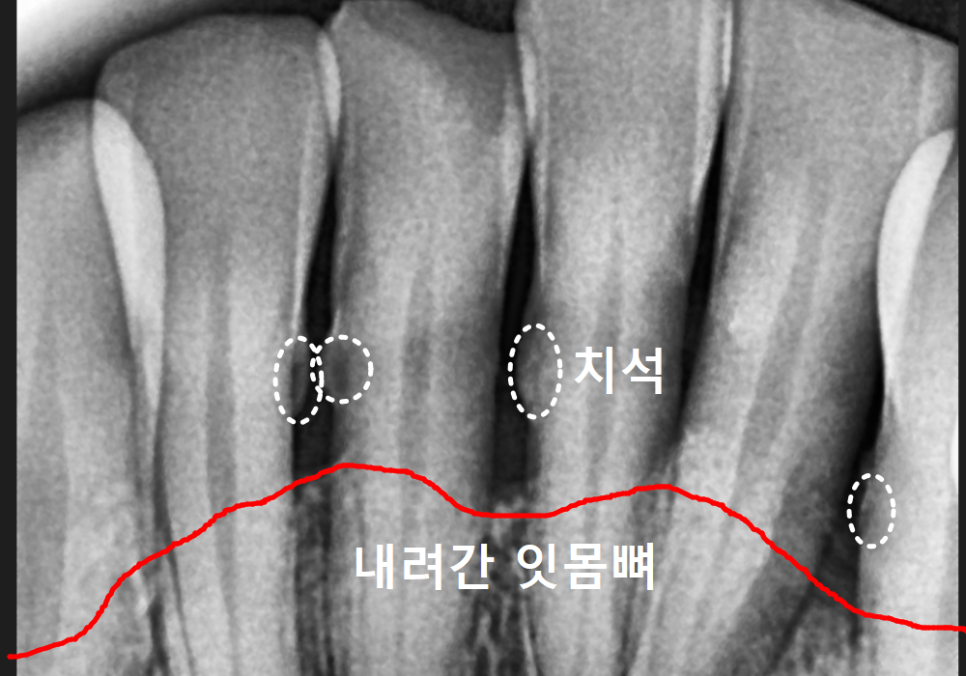

치은연하치석의 위험성

고덕동 스케일링 미루다 앞니 어금니 다 뽑고 임플란트 했습니다.

눈에 보이는 치석보다 더 무서운 것이

바로 잇몸 라인 아래쪽에 숨어있는

'치은연하치석'이에요.

이 치석들은 잇몸 깊숙한 곳에 자리 잡아

점점 잇몸뼈를 녹입니다.

이렇게 잇몸 안쪽까지 파고든 치석은

치아를 지탱하는 힘을 약화시켜

결국 멀쩡해 보이던 치아를 흔들리게 만듭니다.

#47 치아: 수직 파절(완전히 쪼개짐)

#47,46,45, #31,32,33, #16,14 : 치아흔들림

전체적인 상태: 잇몸뼈가 녹아

치조골 수평이 매우 낮아진 상태